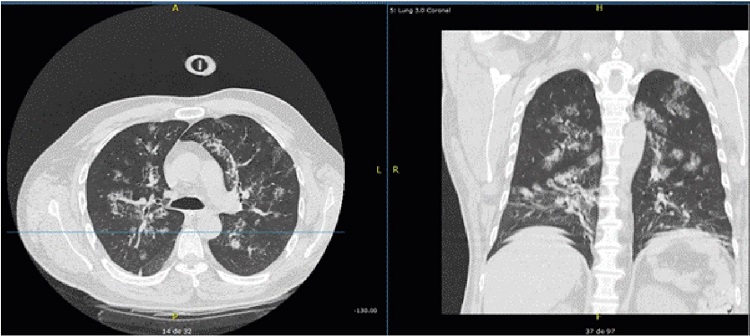

Además, como parte de los estudios de extensión, se ordenó tomografía computarizada de tórax, la que documentó áreas con aumento de la atenuación en vidrio esmerilado distribuidas en forma parchada en ambos campos pulmonares, con predominio central (figura 3). Se hicieron lavado broncoalveolar y cultivo. No se obtuvo aislamiento de Nocardia spp. La prueba molecular de identificación de Mycobacterium tuberculosis y el cultivo para micobacterias fueron negativos. Asimismo, la prueba rápida de HIV fue negativa y el recuento de linfocitos T CD3, CD4 y CD8 no demostró ninguna alteración.